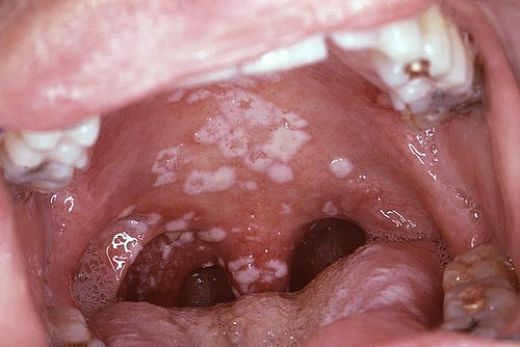

White Spots On Throat Or Tonsils Causes And Treatments

Food allergy white spots on throat. I have a big white spot in the back of my throat in front of the uvula and a small white spot on one of my tonsils. These dots can be a result of medical reactions occurring from development of oral yeast to bacterial infections. Leukoplakia Leukoplakia is an oral precancerous lesion which happens to be yet another cause of white spots.

Although they dont form the stones directly almost all types of allergies do promote the formation of tonsil stones. Does an Allergy cause tonsil stones. Appearance of white spots or patches in your throat can be disconcerting especially if you are developing other symptoms.

While nutritional deficiencies allergic reactions tobacco chewing and smoking are considered to be the likely causes of this condition none have been conclusively proven as yet. However food intolerance does not involve the immune system and does not cause severe allergic reactions known as anaphylaxis. White spots or sores at the back of the throat.

Symptoms of throat ulcers These include. Food intolerance also does not show on allergy testing. White spots in your throat are not always due to infection they may also develop from post-nasal drip dry air or allergic reactions.